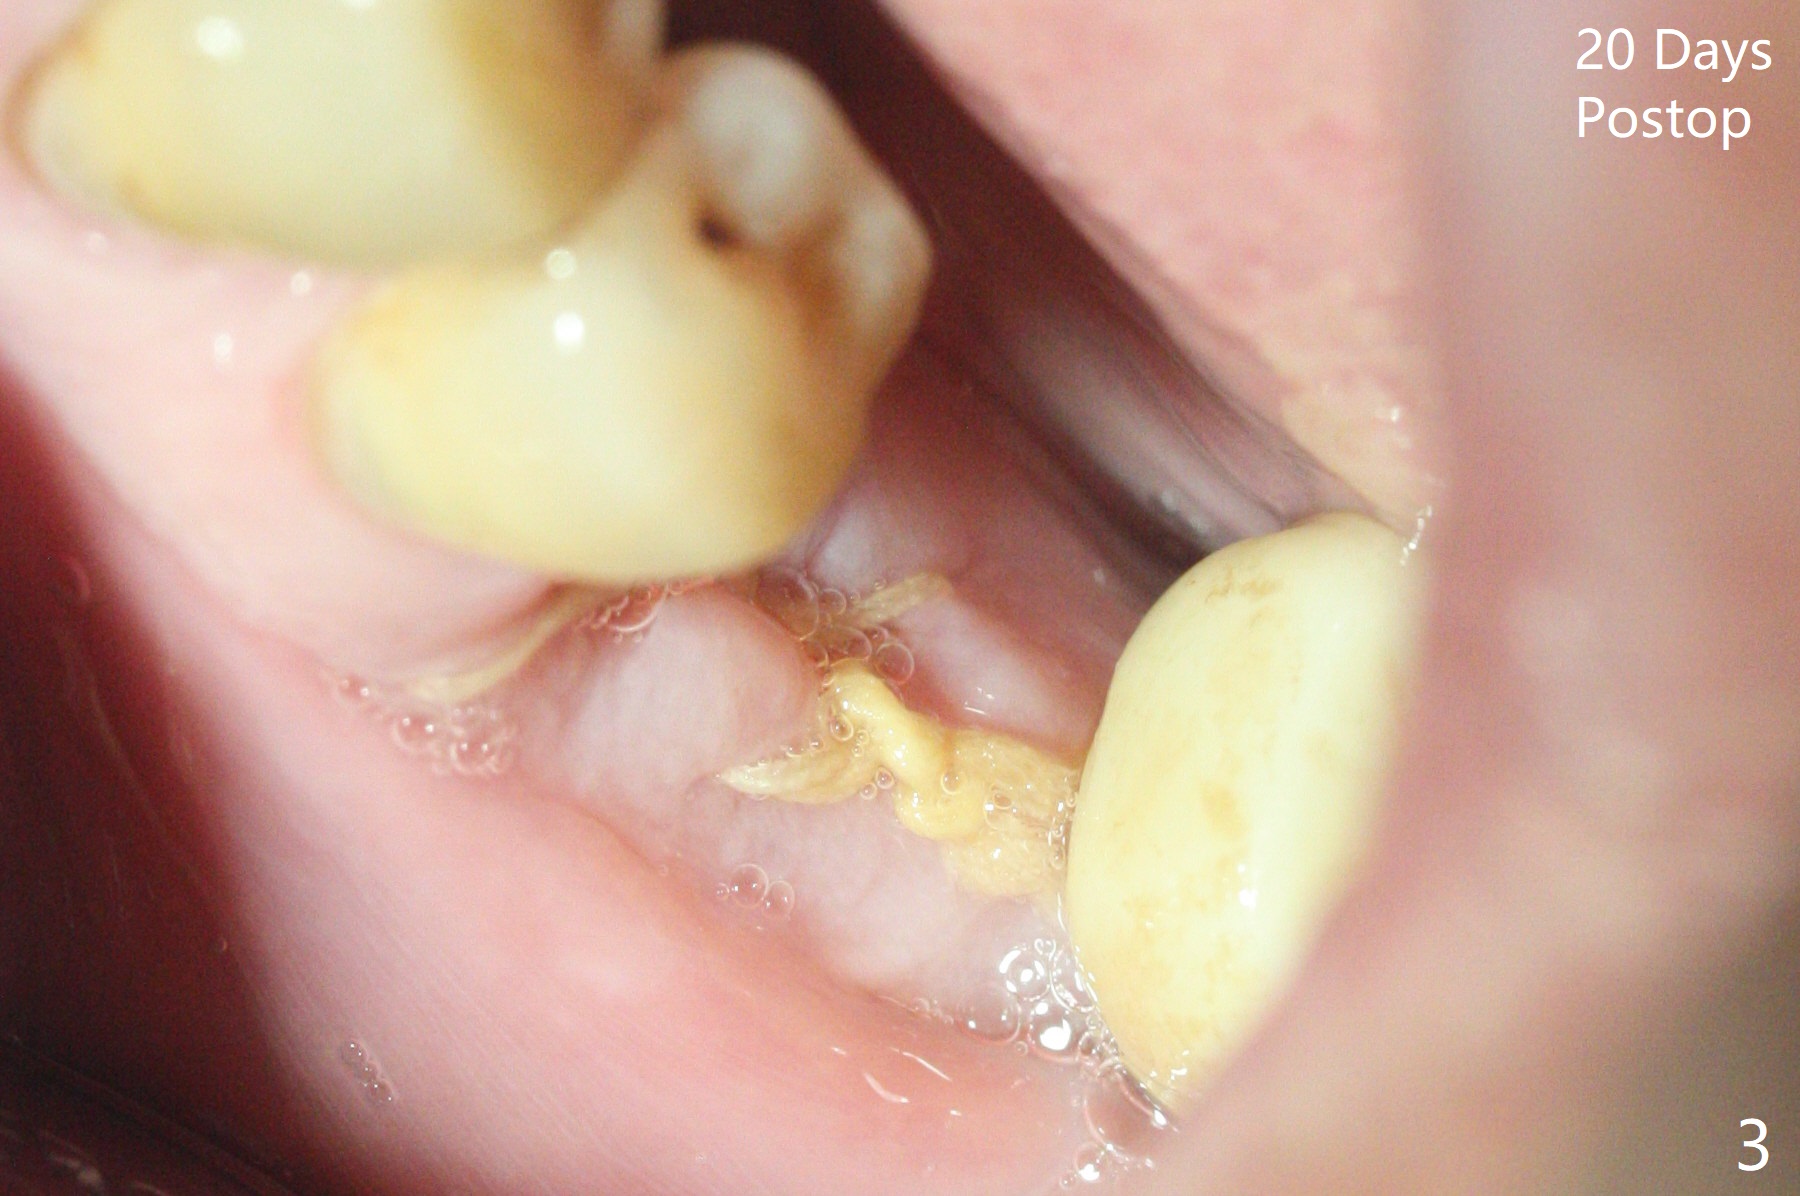

A 58-year-old man requests extraction of the tooth #19 with supraocclusion (Fig.1). After extraction, the septal gingiva has to be sectioned to remove underlying granulation tissue thoroughly. The buccal plate is missing. Ossogen (allograft, Fig.2 *) is placed around the septum (red dashed line). The socket opening is covered by BioXclude and approximated with 4-0 PGA suture, followed by periodontal dressing. With the septum's support, bone graft is expected to heal without too much ridge collapse. The mesial and distal sockets behave as 2 small premolar ones, getting ample blood supply. The socket heals in 20 days (Fig.3). The sockets heal with preservation of the septum (Fig.4: S), while there is formation of the cortical plate on the top of the ridge 10 months postop (Fig.5: ^). It is safe to place a 5x10 mm implant with guide (Fig.6), whereas it may be necessary to place bone graft lingual to the implant at #18 associated with free hand surgery (Fig.7: >). Return to Lower Molar Immediate Implant, No Deviation 18 种植 位点保存 Xin Wei, DDS, PhD, MS 1st edition 01/22/2020, last revision 07/03/2021